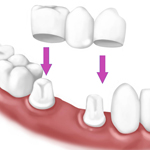

CORONE

Le corone sono protesi per denti singoli dei quali e' conservata la radice. Le corone servono a rimodellare la forma del dente e migliorano la funzionalita' e l'estetica.

La funzione della corona e' quindi quella di proteggere e ripristinare la funzione, la forma ed il colore del dente compromesso e solitamente si ancorano al dente opportunamente preparato (moncone).

I materiali con cui vengono realizzate sono diversi:

- lega bio medicale

- zirconia

- ceramica integrale

- lega nobile oro e porcellana

Ogni soluzione viene studiata dai nostri medici sulla base delle esigenze del singolo paziente.